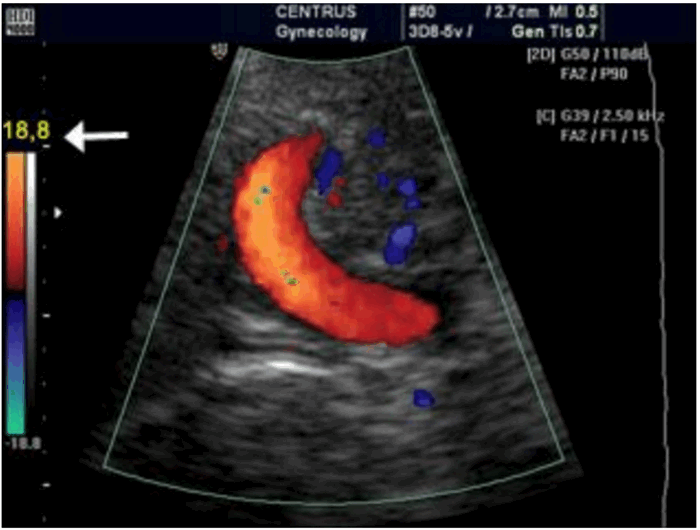

Рисунок 7 (a, b): Цветное допплеровское картирование: влияние частоты повторения импульсов или масштаба цветовой шкалы. а. Установленная низкая частота повторения импульсов, то есть неверный масштаб (отмечен желтой стрелкой). На изображении присутствуют искажения и посторонний шум в пределах контрольного объема пупочной артерии и вены. b. Частота повторения импульсов установлена корректно - масштаб шкалы верный. Цветное изображение показывает артерии и вены четко и без артефактов.